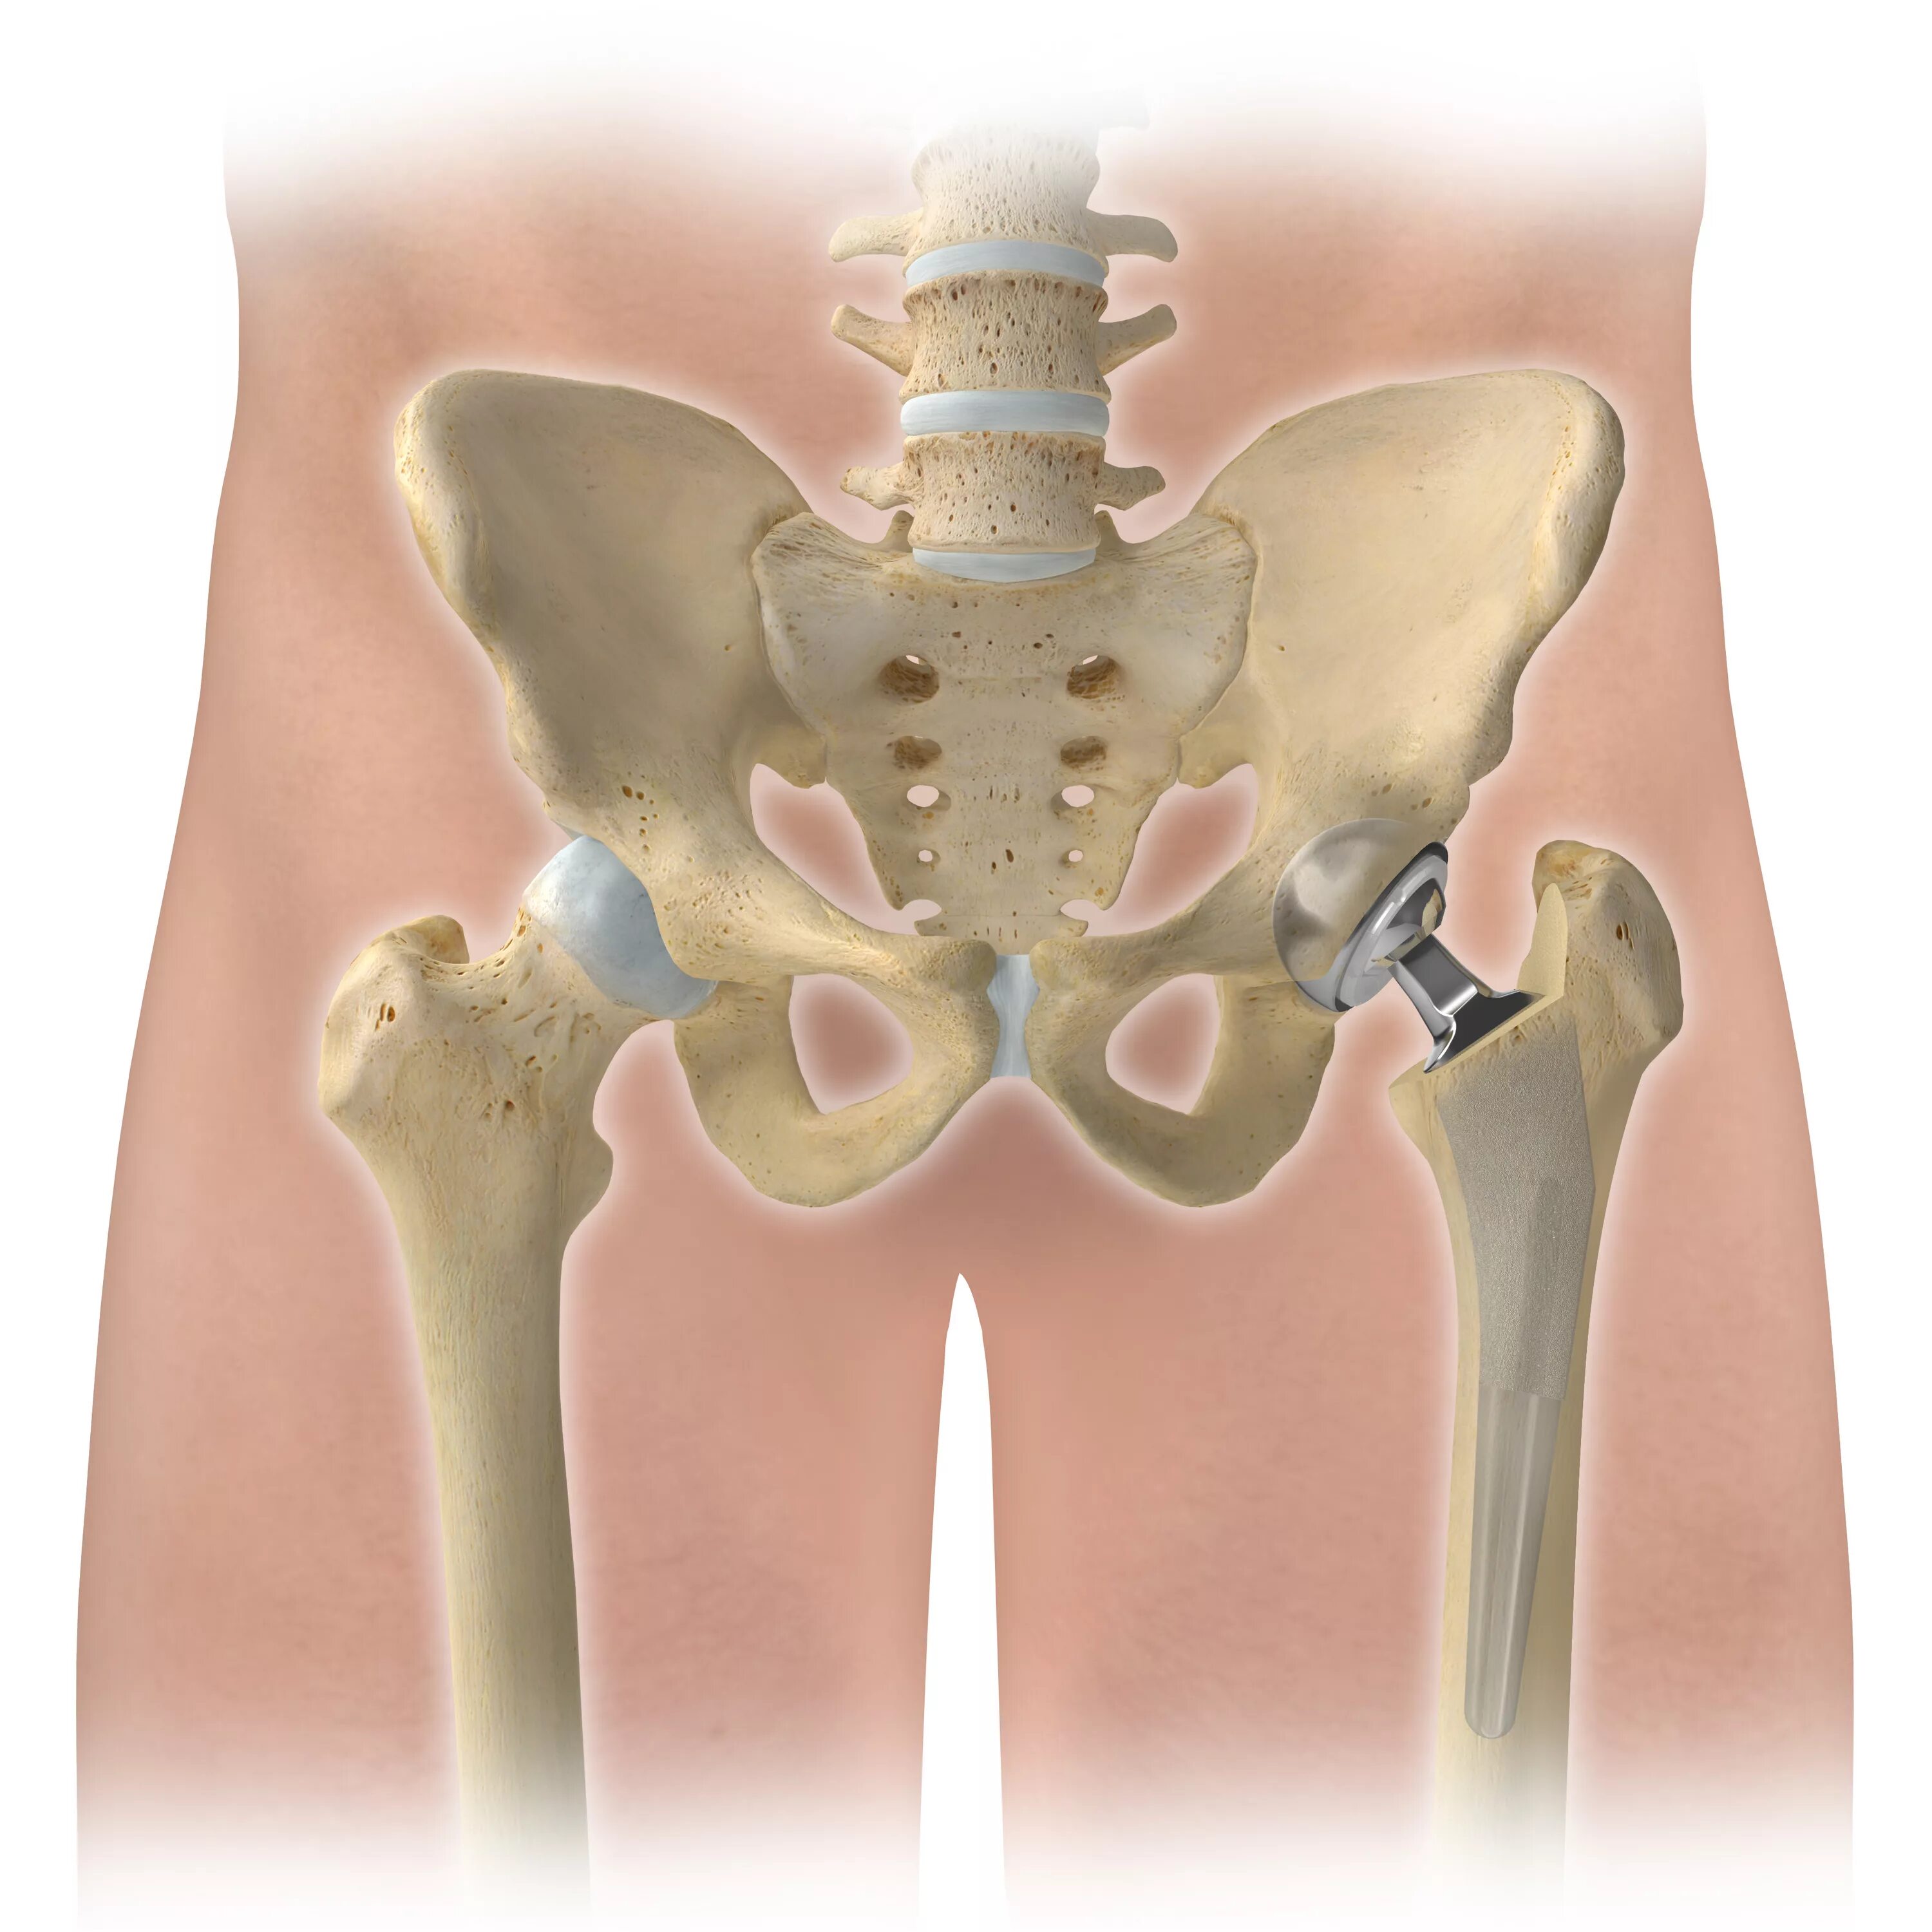

Вывих тазобедренного у взрослых